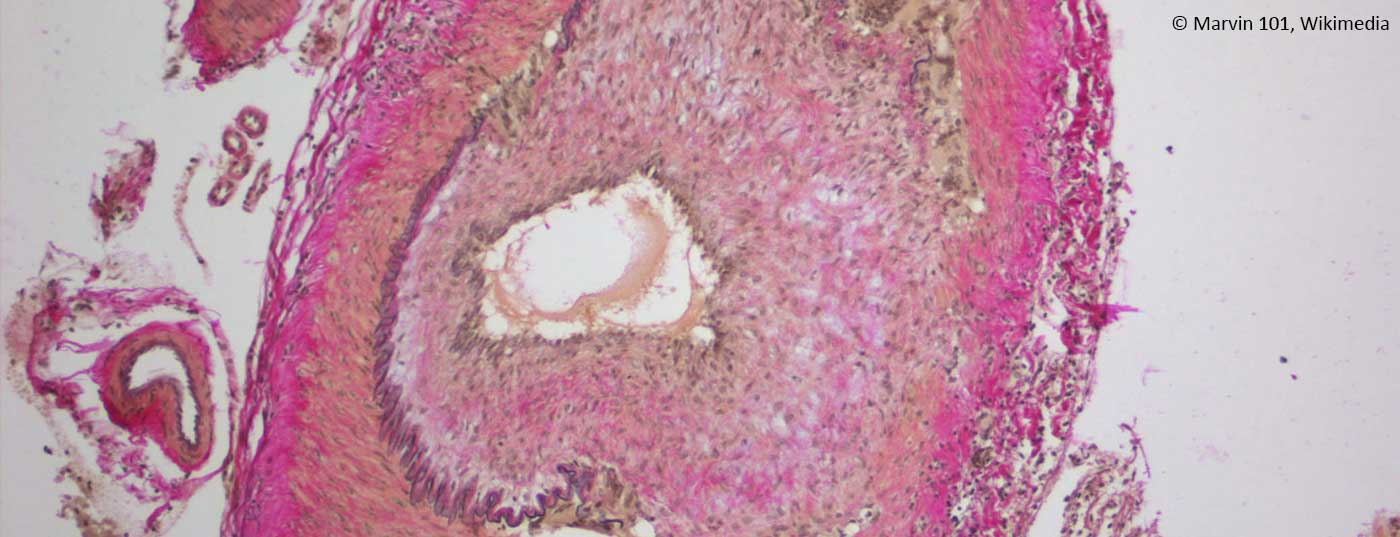

• Autoimmune Entzündung der Temporalarterie

Neues in der Diagnostik und Therapie der Riesenzellarteriitis

Bei Verdacht auf Riesenzellarteriitis sollte unmittelbar eine weitere ­Abklärung und Behandlung erfolgen. Typische Symptome wie Kopf- oder Kauschmerz und Sehstörungen ­können fehlen. Die oligosymptomatische RZA kann mit Bildgebung diagnostiziert ­werden. Die Biopsie der Temporalarterie ist der diagnostische Goldstandart. Der IL-6 Rezeptorantagonist Tocilizumab (Actemra) ist sehr effektiv ­ in der Behandlung von steroidrefraktären Patienten und wird künftig häufiger – und voraussichtlich auch als Primärtherapie – eingesetzt werden.

• Temporalarterie